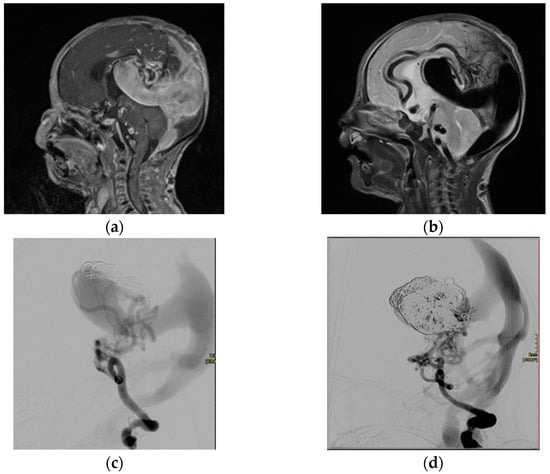

2.1.1. Arteriovenous Malformations